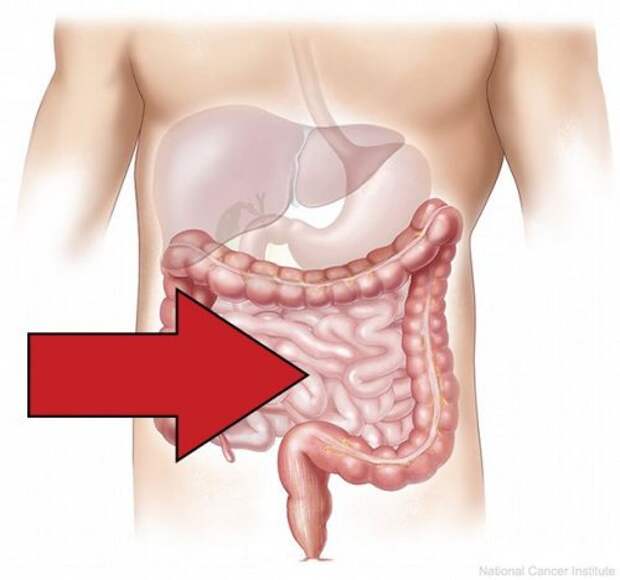

19. Вопреки распространенному мнению, большая часть пищеварительных процессов протекает именно в тонкой кишке, а не в желудке.

Фото: Wikipedia Commons.com

19. Вопреки распространенному мнению, большая часть пищеварительных процессов протекает именно в тонкой кишке, а не в желудке.

11. Ободочная кишка человека состоит из 4 отделов и отвечает за выведение еды из организма после того, как все питательные вещества уже были освоены в предыдущих отделах пищеварительной системы.